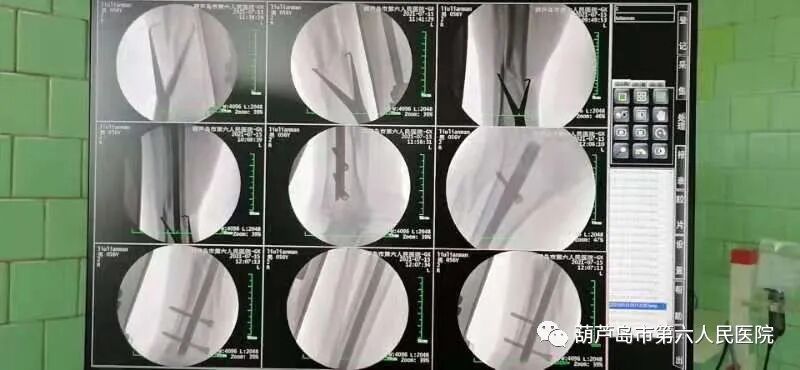

近日,我院骨科在C型臂监控下成功完成了两例“胫腓骨骨折”的微创手术治疗。这是我院引进“高频移动式C型臂X射线机”后的首次投入使用。对比于传统的“髓内钉”手术,使用“C型X射线机”后影像清晰、定位精准、手术效率明显提高(缩短约40分钟手术时间),同时手术创口小,更加利于患者的术后恢复,减少患者痛苦!

结合两名患者的骨折程度及其身体状况,骨科主任决定采用C型臂X射线机下微创手术,借助高频移动式C型臂X射线机的高清性能,高效精准的为病人完成了手术。有着20年骨科手术经验的老主任在使用过后也不禁感慨:“太清楚了,就像是在眼皮子底下接骨,一目了然”!